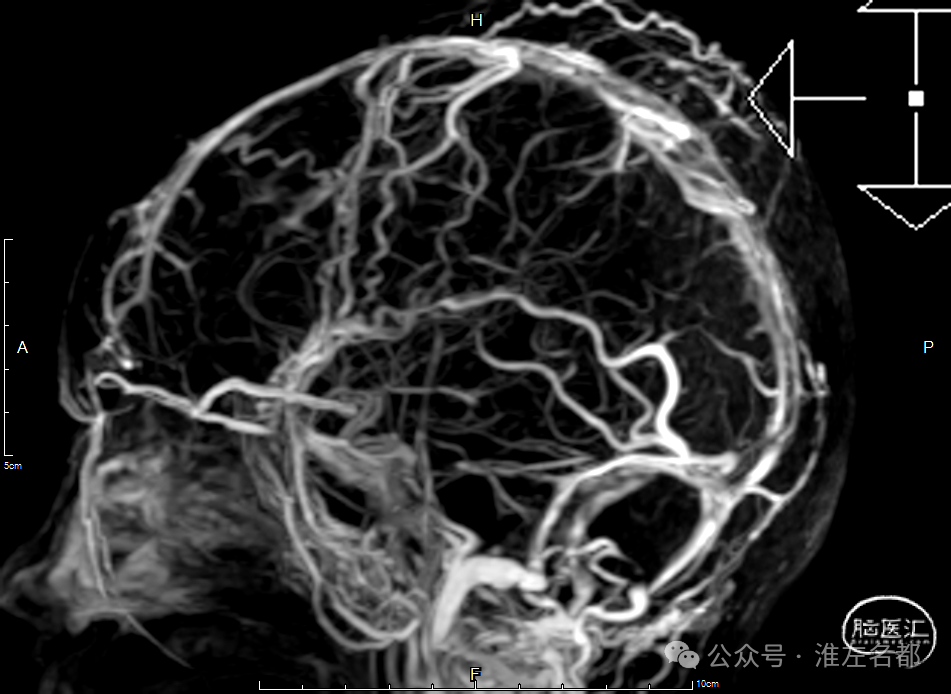

右侧颈动脉造影(正侧位):上矢状窦和直窦未见显影;右侧横窦和乙状窦少许显影。

左侧颈动脉造影(正侧位):上矢状窦前部少许显影,直窦未见显影,左侧横窦和乙状窦显影纤细。

介入治疗后右侧颈动脉造影:上矢状窦、直窦和右侧横窦-乙状窦均见显影,右侧横窦局部狭窄明显。

CTV:上矢状窦、直窦、右侧横窦-乙状窦再通显影,右侧横窦局部管腔狭窄明显。